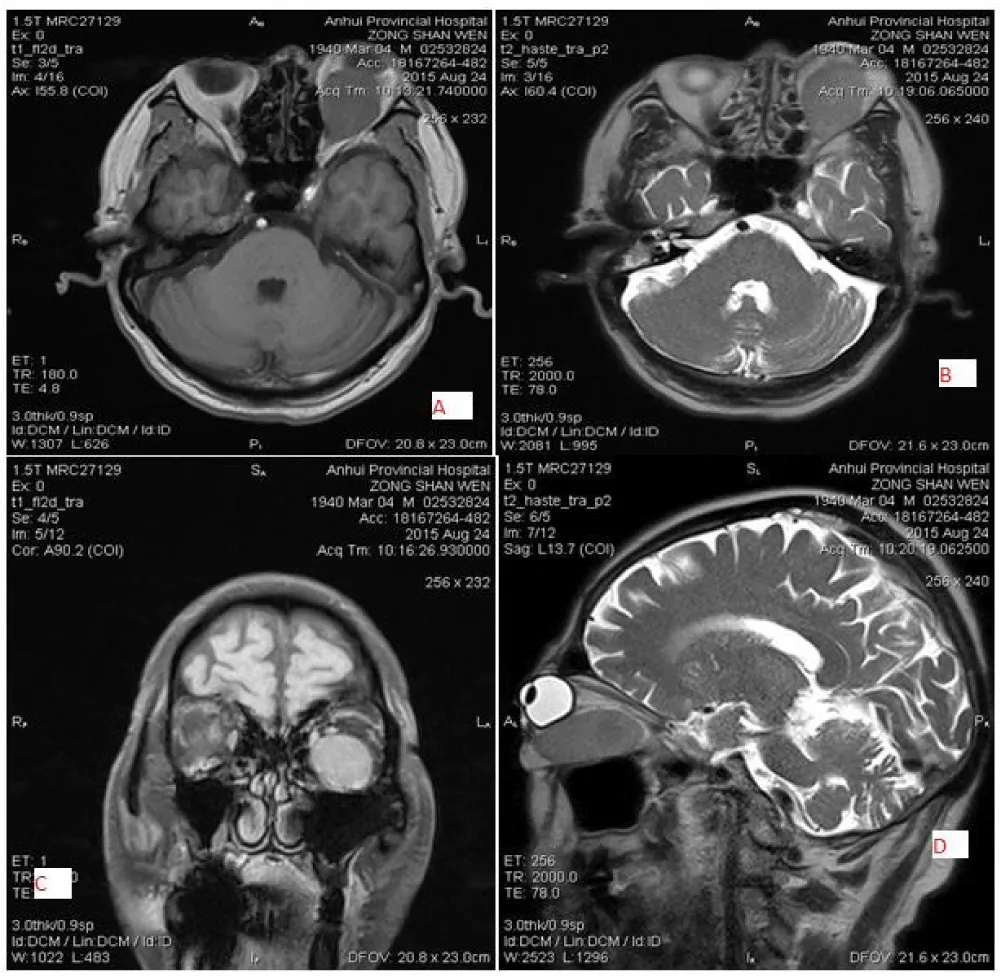

The most common primary optic nerve tumor is optic glioma in children under 5 years old (50%). Optic nerve glioma is a slow-growing, low-grade glioma tumor. 30% of patients with optic glioma have associated NF1, and those individuals have a better prognosis. Orbital meningioma is a slow-growing benign tumor that arises from arachnoid cap cells of the optic nerve sheath. Orbital meningioma can be distinguished from orbital lymphoma by showing less intense enhancement than meningioma, and by moulding around structures, which is present in lymphoma. Additionally, calcification is not seen in lymphoma, but it is frequently seen in orbital meningioma on CT images. Optic glioma is characterized by dilatation or enlargement of the optic nerve, while orbital schwannoma typically overlaps the optic nerve. In contrast, an orbital meningioma surrounds the optic nerve on CT and MRI scans (Figures 2,3).

Download Image

Figure 2: 43-year-old female patient with left-sided meningioma, location surrounding the optic, well-defined and regular shaped, low signal intensity on T1WI (A) and slightly high signal intensity on T2WI(B) and marked homogeneous enhancement(C&D).